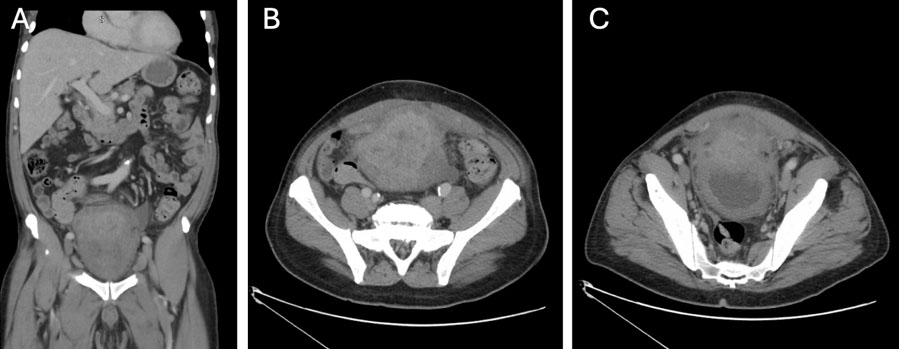

Inguinal hernia is a very common pathology worldwide. Global incidence is about 4–5%. The most commonly involved organs are the abdominal viscera. As far as urology is concerned, urinary bladder is involved in approximately 0.5–4% of all inguinal hernias, while finding the ureters is truly a rarity, about 150 cases worldwide. Ureteral hernias could be an incidental finding but it is important to know about their existence to avoid injury during surgery. We present the case of a 71-year-old man with a finding of right ureteral hernia incidentally diagnosed during computed tomography (CT) scan for an abdominal abscess.